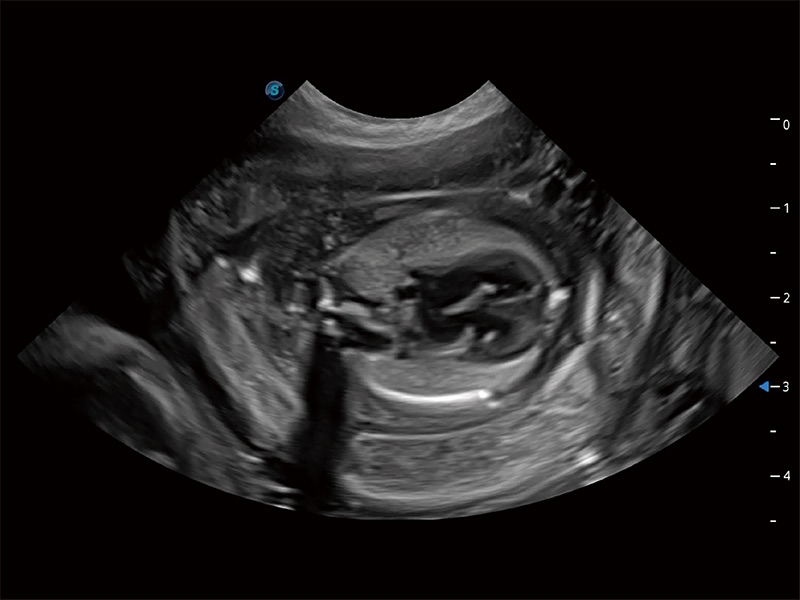

动物是人类最亲密的朋友和最值得信赖的伙伴。玖鼎集团也一直致力于探索动物专用的超声影像解决方案。全新推出的ProPet系列,是玖鼎集团在动物超声影像智能化、专业化、精准化的一次跨越式革新。动物不能用言语来表述自己的不适,通过超声影像,ProPet系列搭建了动物医生与不同物种沟通的“桥梁”,为动物医生注入了“治愈之力”。 ProPet 80 是玖鼎集团匠心打造的一款高端动物专用彩超,采用性能卓越的全新硬件架构,极大提升超声系统的运行效率和数据处理能力,帮助动物医生从容应对日益增多的挑战性病例和日益多样化的临床需求。

高性能和先进的临床应用工具可以为动物医生提供临床信心。ProPet 80 搭载了先进的腹部和浅表应用工具,帮助医生在日常临床实践中发挥前所未有的作用。

ProPet 80 专为动物医生设计,对不同的动物体型和生理结构作出了针对性的优化。通过动物影像专用软件,可满足个性化的应用需求,帮助动物医生获得更精确的诊断数据。